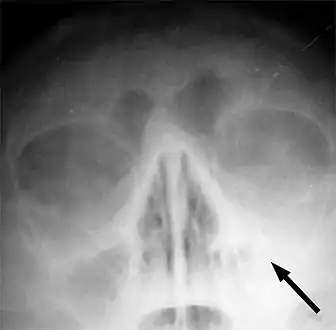

Frontal sinusitis X-ray of left-sided maxillary sinusitis marked by an arrow. There is lack of the air transparency indicating fluid in contrast to the other side.

X-ray of left-sided maxillary sinusitis marked by an arrow. There is lack of the air transparency indicating fluid in contrast to the other side.